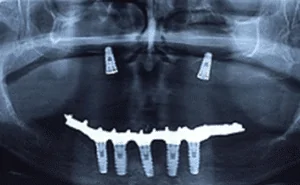

Paciente de 48 anos, do sexo feminino, apresentando boa saúde geral, procurou atendimento odontológico para reabilitação maxilar. A mesma relatou

A reabilitação de maxilas atróficas, onde a quantidade óssea é insuficiente tanto em altura quanto em largura, pode inviabilizar a